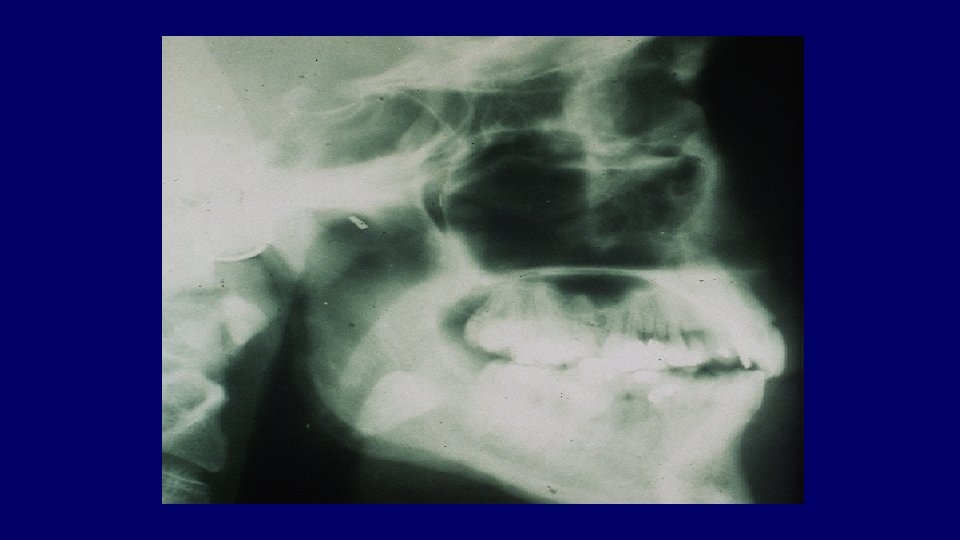

Assessment (Impacted teeth) Radiographic examination • OPG (Orthopantomagraph) • Periapical views • Parallax views • Occlusal views

Mandibular third molar assessment (1) Type of impaction (2) Depth of impaction (3) Root pattern (4) Crown form (5) Bone density (6) Relationship to ID nerve (7) Caries (8) Position and root pattern of 2 nd molar (9) Associated pathology (10)Access

Pell & Gregory Classification • Based on the amount of tooth covered by the anterior border of the ramus • The depth of the impaction relative to the adjacent tooth

Pell & Gregory • Relation to the Ramus Class III

Pell & Gregory • Depth of Impaction – Mandibular Class A Class B Class C

Pell & Gregory